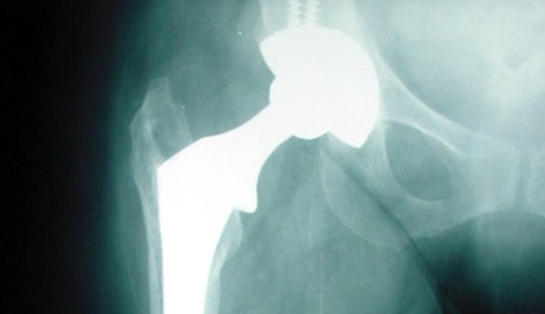

Total kalça protezi nedir

Total kalça protezi, kalça eklemi ileri derecede harap olmuş hastalarda, hasarlı eklemin yapay bir eklemle değiştirilmesi ameliyatıdır. Kalça protez kobalt krom veya titanyumdan imal edilen ana parçalar ile bunların eklemleştiği yerde plastik, metal veya seramik ara parçalardan oluşur.